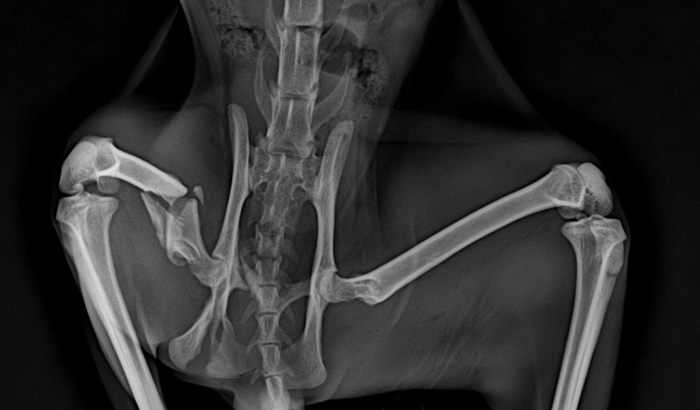

Peço ajuda para custear a cirurgia de um gato de rua que foi atropelado e sofreu uma fratura no fêmur. O procedimento, incluindo medicação, internação por sete dias e exames de raio-X, tem um custo total de R$ 2.000. Ele está em grande sofrimento e precisa de cuidados urgentes. Qualquer contribuição será de imensa ajuda. Obrigado!